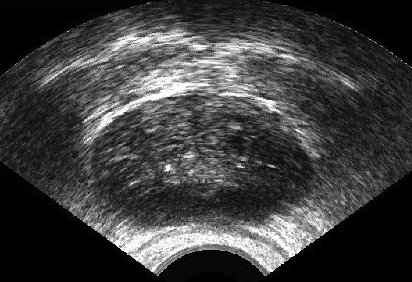

It is a challenge to validate any approach to segmentation. One has to measure the accuracy of the segment against ground-truth images. Ideally, if we have many users available to segment images, we can build “consensus segments”, or gold standard, to make more reliable measurements. Of course, this is usually not feasible with real images, for which there is no gold standard. Hence, we generated synthetic images whose gold segments were known a priori. For this reason, we used synthetic images that simulate transrectal ultrasound (TRUS).

TRUS images of prostates may be used to both diagnose and treat prostate diseases such as cancer. Starting with a set of prostate shapes , we created random segments through combinations of those priors, adding noise along with random translations and rotations, and we distorted the results with speckle noise and shadow patterns. Each image is thus created from its gold . Consequently, we can simulate user delineations by manipulating via scaling, rotation, and morphological changes, and we can simulate edits by running active contours with variable user-simulating parameters. The variability of user delineations was simulated according to several factors: error probability (), anatomical difficulty ( out of ), and the scaling factor for morphology (form to ). The user was modelled according to the level of experience (a random number from ), the user’s attention (a random number from ), and the user’s tendencies in terms of the segment size (a random number from ), whether tending to draw contours that are relatively small () or large ().

We generated 500 images from their corresponding gold-standard images111All images and their segments are available online: http://tizhoosh.uwaterloo.ca/. Furthermore, we generated 20 different segments for each image, assuming that there were 20 users. Figure 4 shows five examples of real and synthetic TRUS images. One should bear in mind that the purpose here was not to simulate the images realistically, but rather to have a base from which to generate variable segments from a perfect segment. Figure 5 shows an example of the gold segments and simulated user contours. The variability, coupled with the gold segment, is what is needed in our experiments.